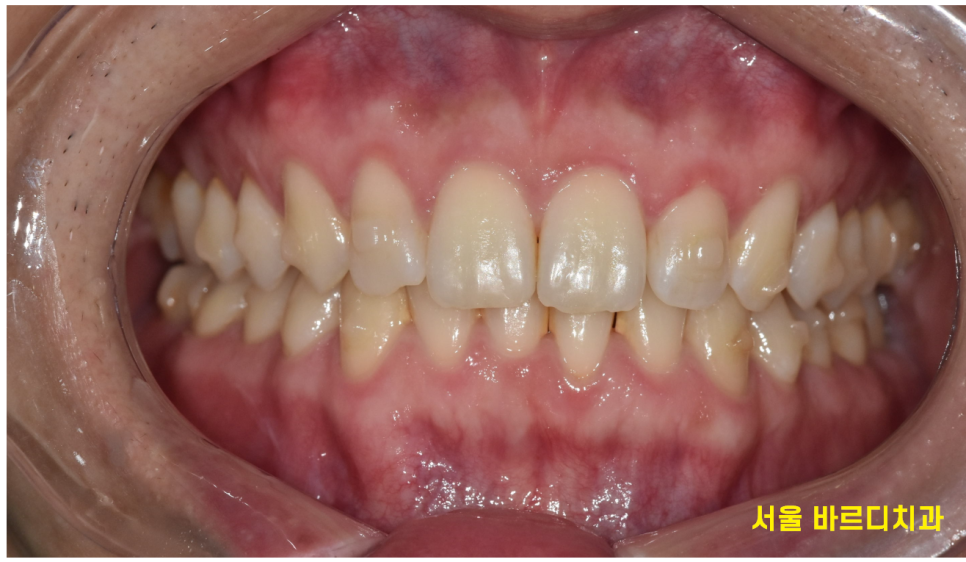

241018 장치 뺸 모습

- 눈에 띄지 않아 군대 생활에 불편함 없음

투명교정의 가장 큰 장점 안보입니다.

외부에서 보이지 않아요~

정말 자세히 보면 모를까...

투명하고 얇은 플라스틱이기 때문에

착용하고 있어도 불편감이 거의 없습니다.

230725 투명교정하는 사람 입이라고는 전혀 모르시겠죠?